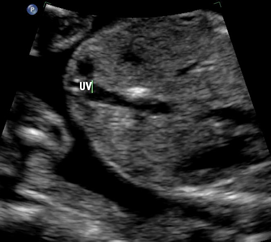

Above. Gestational age is 23 weeks. Isolated hepatic calcification. The calcification measures 4.2 x 7.4 x 6.9 mm. It is adjacent to the hepatic vein.

Above. Gestational age is 23 weeks. Isolated hepatic calcification. Color Doppler demonstrates the relationship of the echogenic focus to the hepatic vein. The lesion was not within the gallbladder and there were no adverse outcomes.